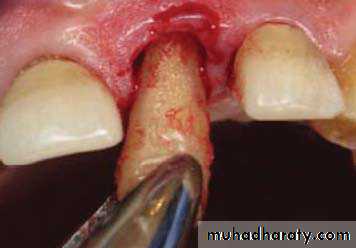

Periotome

What is periotome?One way to reduce trauma to adjacent bone during tooth extraction is via use of the periotome. Periotomes are extraction instruments that employ the mechanisms of “wedging” and “severing” to facilitate tooth removal. Periotomes are composed of very thin metallic blades that are gently wedged down the periodontal ligament (PDL) space in a repetitive circumferential fashion. In addition to minimally invasive luxation, the periotome blade severs Sharpey’s fibers that secure the tooth within the socket.